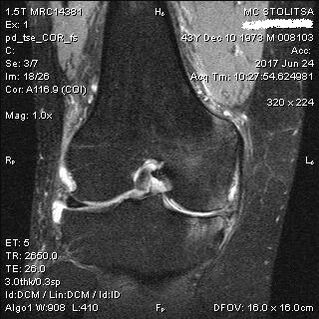

Dijagnoza artroze koljenskog zgloba postavlja se u ordinaciji reumatologa ili ortopeda. Doktor pregleda zahvaćeni zglob, palpira ga, sasluša pritužbe i postavlja dodatna pitanja. Obavlja nekoliko testova - na primjer, traži od pacijenta da savije nogu ili hoda nekoliko koraka. Zatim, ako je potrebno razjasniti stadij bolesti ili prirodu patoloških promjena, uputit će vas na dodatne studije. Na primjer, za kompjutersku tomografiju ili radiografiju.